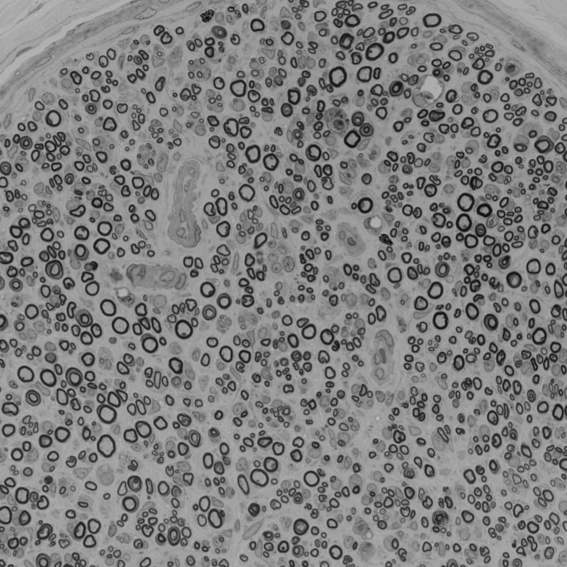

A curated collection of diverse microscopy datasets (TEM, SEM, BF) designed to benchmark and train axon and myelin segmentation models.

Scalebars: TEM1: 1 μm; TEM2: 4 μm; SEM1: 30 μm; BF1: (left) 100 μm, (right) 50 μm; BF2: 50 μm.

SEM1

Rat spinal cord